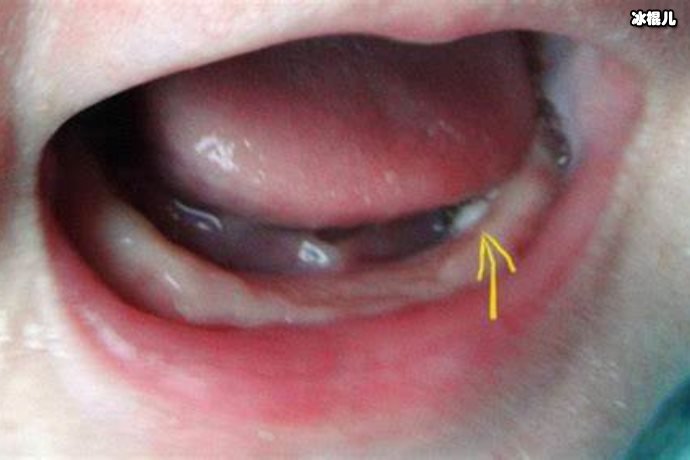

马牙是指宝宝长牙时,由于长牙处的细胞代谢活动增强会导致局部血流量增加、软组织水肿,从而造成牙龈肿胀、发炎、疼痛等现象。注意区分并不是其他疾病引起的牙龈炎,如果牙龈炎症状较重,应去医院检查。

鹅口疮则是由于口腔黏膜受凉或者感染致炎,形成的一种口腔疾病,一般症状为口腔黏膜一侧或两侧出现白斑或带状溃疡,口腔进食时产生疼痛。容易被误认为是马牙所致的炎症,但注意区分后,应及时去医院进行治疗。